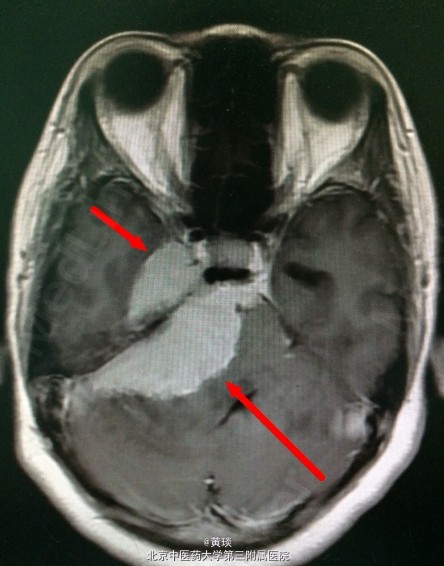

患者47岁,无明显诱因出现头痛1年,无恶心呕吐,无头晕,无呼吸心跳改变,与当地中医院中草药治疗,疗效差,近半月明显加重,遂于我院就诊。

头颅MRI提示:桥小脑角区巨大脑膜瘤

诊断:脑膜瘤 处理:开颅切除